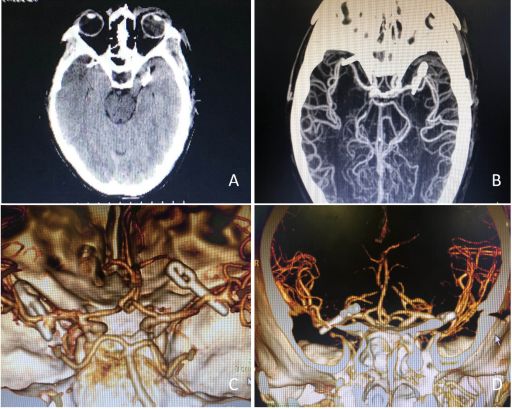

入院后急诊复查头颈部CTA示:左侧大脑中动脉分叉部宽颈动脉瘤,约8.7×8.0mm;右侧大脑中动脉M1段动脉瘤,约3.6×3.2mm;我院头颅CT示:右侧侧裂池蛛网膜下腔出血已基本吸收。

图1入院后急诊行头部CTA检查结果提示颅内多发动脉瘤(A)当地医院头颅CT提示右侧侧裂池蛛网膜下腔出血;(B)头颅CTA检查提示左侧中动脉分叉部动脉瘤,瘤颈宽;(C)头颅CTA提示右侧大脑中动脉M1段动脉瘤,为责任动脉瘤,瘤体朝向蝶骨嵴(D)右侧瘤颈距离中动脉起始部长达24mm (E)左侧大脑中动脉分叉部宽颈动脉瘤,约8.7×8.0mm(F)右侧大脑中动脉M1段动脉瘤,约3.6×3.2mm